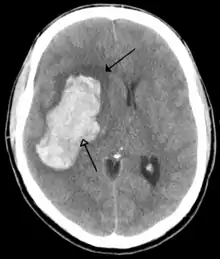

Most strokes result from loss of blood supply, typically because of an embolus, rupture of a fatty plaque causing thrombus, or narrowing of small arteries. Strokes can also result from bleeding within the brain.[190] Transient ischaemic attacks (TIAs) are strokes in which symptoms resolve within 24 hours.[190] Investigation into the stroke will involve a medical examination (including a neurological examination) and the taking of a medical history, focusing on the duration of the symptoms and risk factors (including high blood pressure, atrial fibrillation, and smoking).[191] Further investigation is needed in younger patients.[192] An ECG and biotelemetry may be conducted to identify atrial fibrillation; an ultrasound can investigate narrowing of the carotid arteries; an echocardiogram can be used to look for clots within the heart, diseases of the heart valves or the presence of a patent foramen ovale.[192] Blood tests are routinely done as part of the workup including diabetes tests and a lipid profile.[192]

Some treatments for stroke are time-critical. These include clot dissolution or surgical removal of a clot for ischaemic strokes, and decompression for haemorrhagic strokes.[193][194] As stroke is time critical,[195] hospitals and even pre-hospital care of stroke involves expedited investigations – usually a CT scan to investigate for a haemorrhagic stroke and a CT or MR angiogram to evaluate arteries that supply the brain.[192] MRI scans, not as widely available, may be able to demonstrate the affected area of the brain more accurately, particularly with ischaemic stroke.[192]